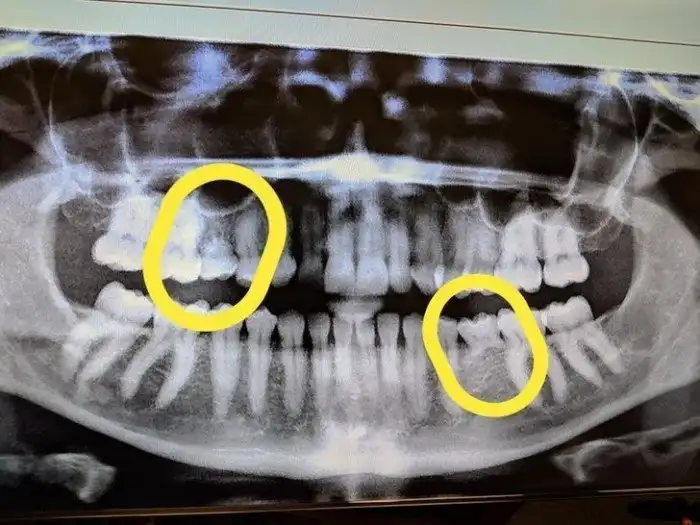

14. "Зубная фея должна мне много денег. Мне 33 года, и вот мои рентгеновские снимки, на которых видны оставшиеся молочные зубы"